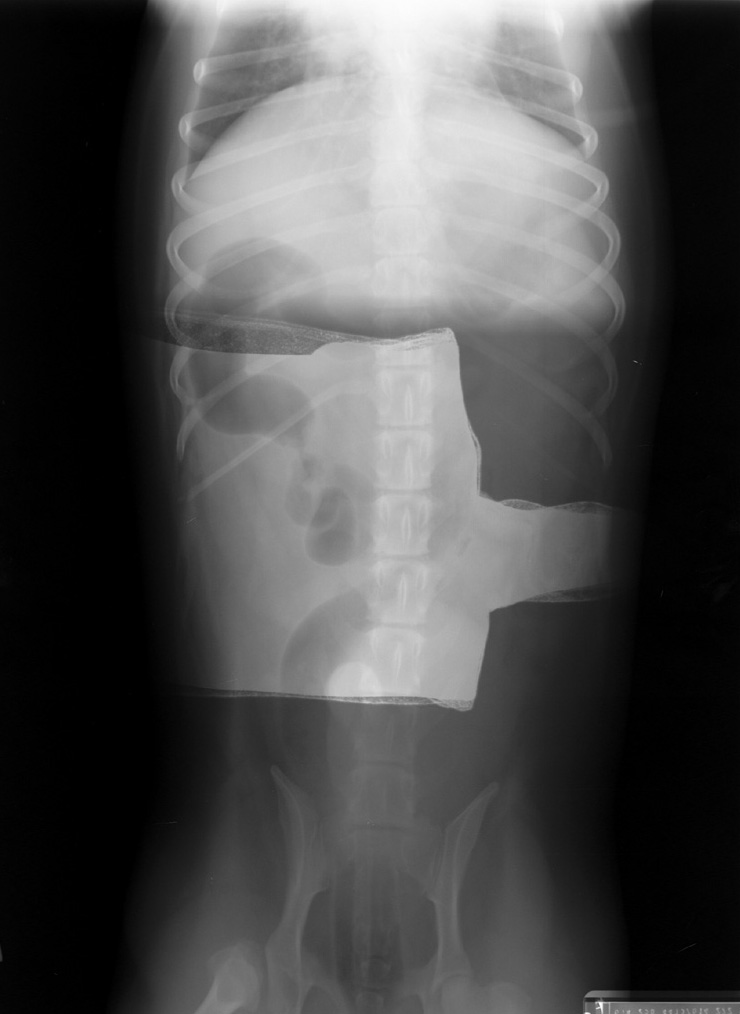

Click to enlarge

Fogged film with glove (lead) overlying part of body

Film was left out on table while other films were being taken and was fogged by scatter radiation. It was then used to make an exposure of a dog's abdomen.